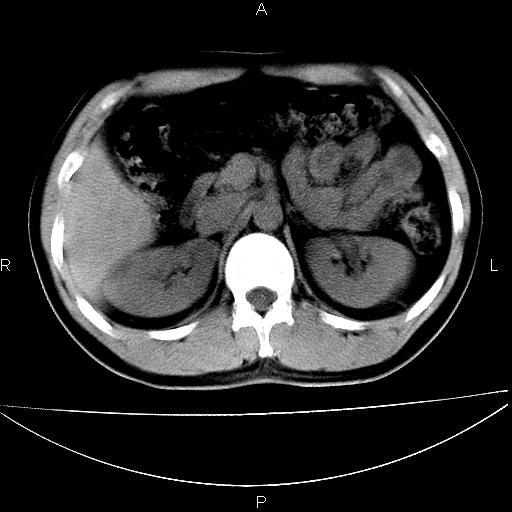

男 25岁 自述 尿频尿急,排尿困难20多天.无腰痛, b超说左肾盂轻度积水,左输尿管上端扩张.未见结石影. ct我看双侧肾盂轻度积水,双输尿管上端都扩张,大家看看能看见结石吗?

双肾轻度积水,双侧输尿管上段扩张(原因待查)。

双肾盂及双输尿上段轻度积水,双输尿管未见明显结石影。

双肾盂及双输尿上段轻度积水